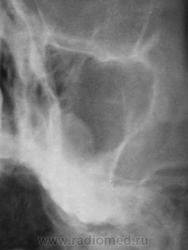

Пациент первый.

Киста, или что другое?

Больше похоже на кисту. Четкий округлый контур с характерным месторасположением. Хотя может и не так все просто)

да,  похоже на кисту, но справа снижена пневматизация верхнечел.пазухи за счет умеренного отека, я бы кисту слева под вопросом написала и направила на контроль

---------------------------------------------------------------------------------------------------------------------------------------------------------------------------------+1: как вариант,  можно предположить, что киста одонтогенного происхождения.